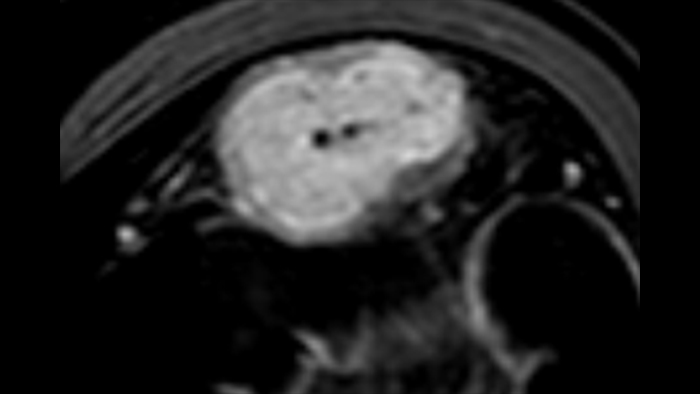

Les images sont absolument différentes selon l’état inflammatoire. C’est une question de densité, de pulsatilité, mais également de localisation des vaisseaux. C’est l’avantage de la superposition des images de micro-flux à celles des couches pariétales obtenues par échographie haute résolution. Sur les images suivantes, accompagnées des clichés d’IRM correspondants, il semble que dans le premier cas, à savoir une maladie de Crohn d’apparition récente, les vaisseaux soient localisés à la surface de la paroi intestinale, probablement au niveau de la muqueuse. En revanche, dans les autres cas de maladie plus avancée, ils sont également plus visibles à l’intérieur de la sous-muqueuse et dans le tissu adipeux adjacent.

Mucosa

Submucosa

Adjacent fat

Dans cette forme tardive et probablement fibreuse de la maladie de Crohn, la sous-muqueuse comporte peu de microvaisseaux, tandis que l’ensemble de la paroi intestinale enflammée adjacente à la fistule présente une micro-vascularisation intense.